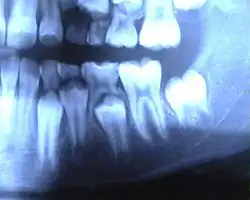

Les dents temporaires sont la première des deux séries de dents qu'ont consécutivement les animaux diphyodontes, comprenant la plupart des mammifères. Chez certaines espèces, toutes ou une partie des dents temporaires sont perdues durant la vie intra-utérine, c'est notamment le cas du phoque, de l'otarie ou de la plupart des rongeurs pour lesquels la perte a lieu peu avant ou après la naissance[1], chez les cétacés odontocètes, la seconde série est atrophiée et ne pousse jamais. Chez l'Homme, ces dents sont appelées dent déciduale (du latin : deciduus signifiant « qui tombe »), dent de lait ou dent lactéale. Elles surviennent chez l'enfant entre six et huit mois et tombent entre six et douze ans pour laisser la place aux dents permanentes.

L'humain possède 20 dents de lait : 8 incisives, 4 canines et 8 molaires.

Le début de la calcification (début de la formation) se fait au 5e ou 6e mois de grossesse pour toutes les dents de lait. La première dent apparaît en bouche vers le sixième mois après la naissance ; mais elle peut être présente dès la naissance. Parfois une telle dent présente à la naissance est en fait une dent supplémentaire, qui va tomber rapidement. La première perte de dent de lait survient vers six ans.

- Incisives centrales : éruption à 6-10 mois / chute à 6-8 ans

- Incisives latérales : éruption à 8-12 mois / chute à 7-9 ans

- Canines : éruption à 18-24 mois / chute à 9-12 ans

- Première molaire : éruption à 12-18 mois / chute à 9-11 ans

- Deuxième molaire : éruption à 24-30 mois / chute à 10-12 ans

- Couronne : teinte plus claire ; cuspides plus pointues, dents plus globuleuses, rétrécissement cervical (collet) moins marqué.

- Racines : plus fines et plus divergentes, laissant place au germe sous-jacent de la dent permanente.

- Émail : plus mince, moins minéralisé, moins translucide.

- Dentine : tubuli plus gros et plus nombreux. Ceci favorise une progression rapide des caries.

- Pulpe : chambre pulpaire très volumineuse ; communication pulpo-parodontale facile permettent une atteinte de furcation rapide ; la communication infectieuse est favorisée